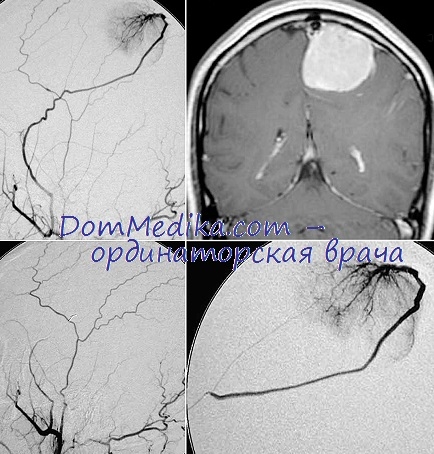

Пухлини головного мозку з інсультообразно плином. Одним з найважчих розділів неврології є диференціальна діагностика пухлин і судинних захворювань мозку. Це питання в даний час має не тільки академічний інтерес, а й суто практичне значення в зв'язку зі значними успіхами в лікуванні пухлинних захворювань, з розвитком судинної хірургії, особливо при патології магістральних судин, а також з сучасними можливостями диференційованої терапії різних типів інсультів.

Майже постійна наявність судинного атеросклеротичного процесу у осіб похилого віку обумовлює частоту крововиливів у тканину самої пухлини, а також в значній віддалі від неї і призводить до інсультообразно течією новоутворень головного мозку. Подібний дебют гліобластоми головного мозку спостерігається майже в 10% випадків пухлин.

Основним для диференціальної діагностики на користь пухлини є динамічне спостереження за хворим, при якому виявляється наростання загальномозкових явищ при відсутності погіршення стану серцево-судинної системи, посилення млявості, оглушення, завантаженості, а також позитивні дані параклінічних досліджень (електроенцефалографія, ехоенцефалографія). Остаточно верифікують діагноз на підставі ангіографії і вентрикулографії.